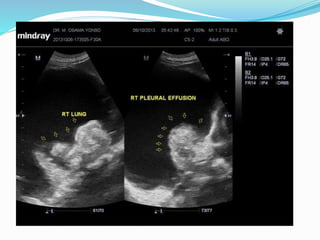

 Ultrasound

 Ultrasound allows the detection of small amounts of

pleural locular fluid, with positive identification of amounts

as small as 3 to 5 ml, that cannot be identified by x-rays,

which is only capable of detecting volumes above 50 ml

of liquid. Contrary to the radiological method, ultrasound

allows an easy differentiation of loculated pleural fluid

and thickened pleura. Moreover, it is effective in

guiding thoracentesis (thoracocentesis), even in small

fluid collections .

 The ultrasound image of pleural effusion is characterised

by an echo-free space between the visceral and parietal

pleura. Septations may be seen in the pleural fluid, and

may indicate underlying infection but can be seen in

chylothorax or haemothorax